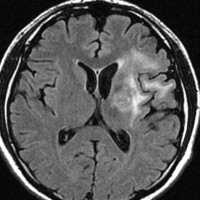

放射線治療後7週目

フレア画像です。腫瘍サイズが増大しています。もともと腫瘍周辺浮腫はなかったのですが大脳基底核と視床に浮腫が出現しています。スード・プログレッションの始まりです。